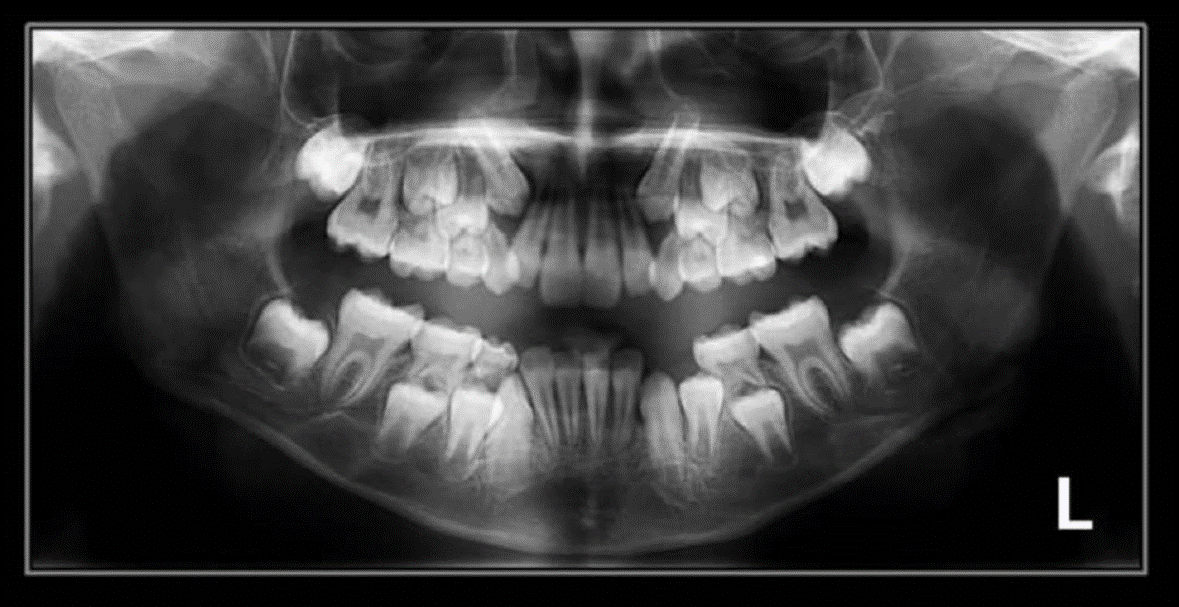

2. How old is the patient with the following X ray?